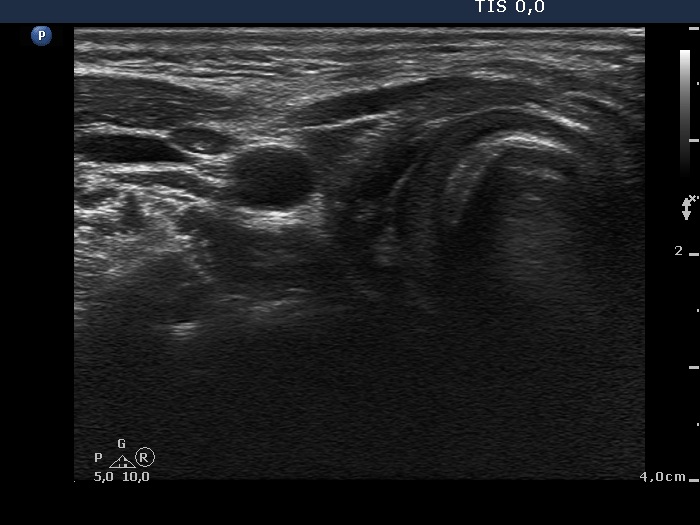

First examination - before surgery (1st and 2nd rows of images)

Ultrasonography. The thyroid was moderately hypoechogenic. There was a small nodule in the ventral part of the right lobe. It was hypoechogenic and presented microcalcifications. The vascularization was not specific.Aspiration cytology was performed from the nodule. Monolayered sheets predominated the smear, microfollicles were found, too. A few nuclei contained inclusions and grooves. The pattern itself was not sufficient to raise the suspicion of malignancy.

Taking the ultrasound presentation into account we gave a common ultrasound-cytological diagnosis of suspicion of papillary carcinoma and Hashimoto's thyroiditis.